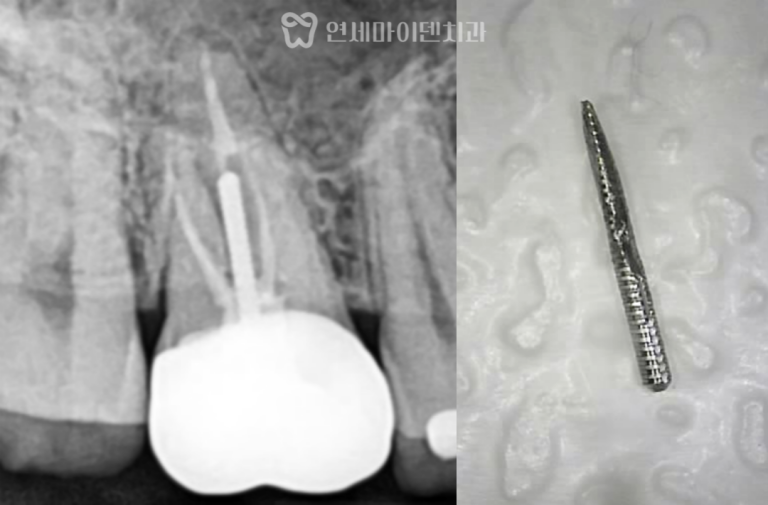

재신경치료 3년 증례: 금속포스트 제거 “신경치료는 한 번 하면 끝 아닌가요?”“이미 쇠기둥 박혀 있다는데, 다시 치료…